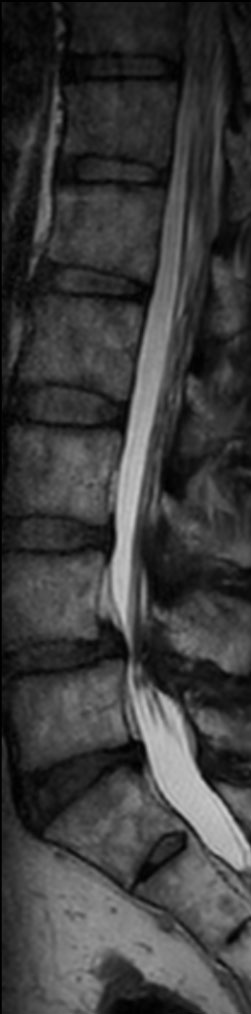

Lumbar Spine disc herniation

Patient with a lumbar spine disc herniation.